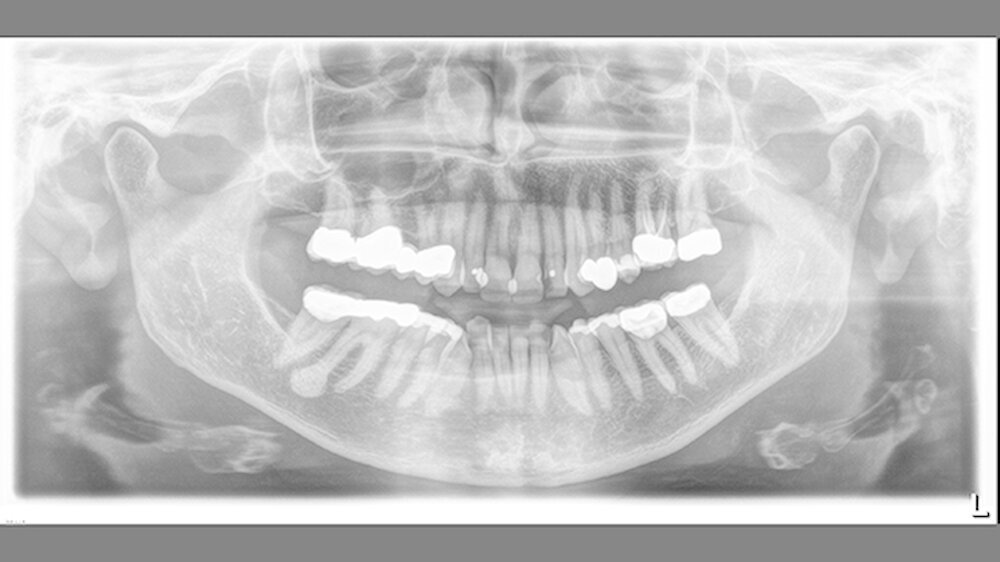

Bei einer erneuten röntgenologischen Untersuchung am 17.8.2015 hatte sich die Verschattung deutlich vergrößert und in ihrer Form verändert. Nun imponierte eine birnenförmige, gleichmäßig strukturierte, feinkörnig-dichte Raumforderung in Verbindung mit einer starken Auftreibung der Wurzelspitze und caudal davon eine halbmondförmige gleichartige Struktur getrennt durch einen sehr feinen Spalt.

Der Zahn 46 reagierte immer noch eindeutig vital auf den durchgeführten Kältetest. Palpatorisch war im Bereich der distalen Wurzel des 46 vestibulär eine harte und nicht druckdolente Auftreibung zu tasten. Es gab keinerlei Anzeichen einer akuten Entzündung. Auch die regionalen submandibulären Lymphknoten waren unauffällig. Eine vorgeschlagene DVT lehnte die Patientin aus Kostengründen ab.